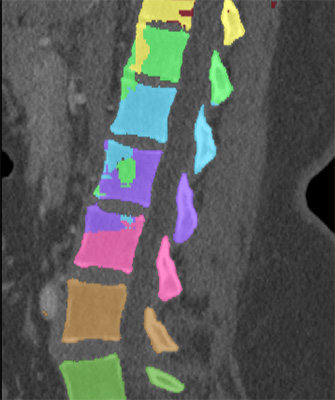

We trained and evaluated the method with five sets of CT and MR scans that visualize the spine. Reference segmentation masks for four of these datasets are publicly available, which allowed for a comparison with other publications that used the same data. Examples of images from the datasets are shown in Figure 3.

Similar performance was achieved for vertebra segmentation in various CT datasets with an average Dice score of and for vertebral body segmentation in an MR dataset with an average Dice score of . Surface distances were lower on CT images compared to MR images ( vs. ), however, there were also fewer training scans available in the MR dataset. Figure 4 illustrates the magnitude of differences of the automatic segmentations from the ground truth segmentations.

(a) Low-dose chest CT

(b) Lumbar spine CT (xVertSeg.v1 dataset)

(c) Lumbar spine MR

In the CT datasets, the segmentation was more accurate on high-resolution dedicated spine scans of healthy subjects compared with low-dose low-resolution chest CT scans and scans of subjects with in some cases severe compression fractures. This is also visible in the segmentation performance stratified by vertebra (Figure 5). Segmentations were more accurate for the lumbar (L1-L5) than for the thoracic vertebrae (T1-T12), which are covered by the more challenging low-dose chest CT scans. Outliers among the lumbar vertebrae correspond to vertebrae from the xVertSeg.v1 dataset, which features a number of severely deformed lumbar vertebrae that are particularly challenging to segment.